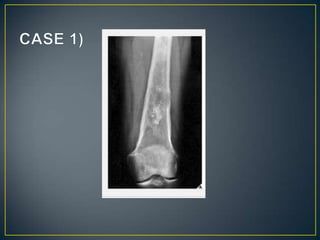

• The site of a bone lesion is an important feature, because

some tumors have a predilection for specific bones or

specific sites in the bone .The sites of some lesions are

so characteristic that a diagnosis can be suggested on

this basis alone, as in the case of parosteal

osteosarcoma or chondroblastoma . Moreover, certain

entities can be readily excluded from the differential

diagnosis on the basis of the lesion's location

• The type of bone destruction caused by a tumor is

primarily related to the tumor growth rate.

• Not pathognomonic for any specific neoplasm.

• Geographic.

• Moth Eaten.

• Permeative.